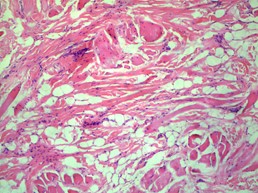

Histopathology of the specimen was notable for abundant haphazard bundles of mature striated muscle admixed with adipose tissue, sclerotic collagen bundles, nerve bundles, and prominent folliculosebaceous adnexa within the reticular dermis and subcutaneous tissue (Figures 1, 2). There was no evidence of cystic elements or malignancy on histopathologic evaluation. Thus, the histopathologic findings were consistent with a diagnosis of RMH.

Figure 2(a,b): Proliferation of well differentiated skeletal muscle within the dermal and subcutaneous layers can be appreciated at high power fields (100x).